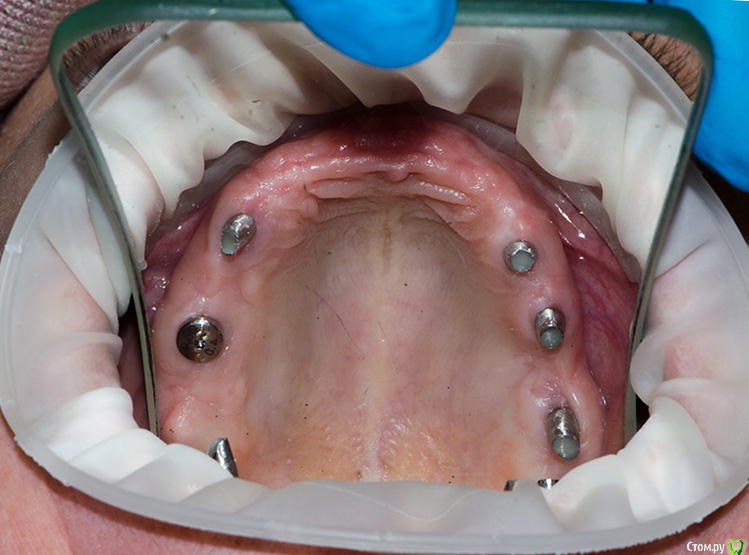

Romanson Опубликовано 30 ноября, 2017 Поделиться Опубликовано 30 ноября, 2017 (изменено) Иногда хочется задать вопрос, но вроде пустяковый и отдельную тему заводить не хочется.Если админы сочтут удалите.Ну а пока начну таким вопросом:Пришла пациентка, хочет циркониевую подкову, на цементе на эти абатменты. Взялись бы? Изменено 30 ноября, 2017 пользователем Romanson Ссылка на комментарий

AndyAndy Опубликовано 30 ноября, 2017 Поделиться Опубликовано 30 ноября, 2017 Нет. Для циркониевой подковы маловато и расположение удачным не назовёшь. Абатменты полированные, должны быть отпескоструенные (супрагингивальная часть). А вообще.... не очень охотно брался бы за такую работу. Из других соображений. Есть такое выражение - кто последний - тот и папа. Очень рискуете потом в случае осложнений переделывать ещё и работу неизвестного хирурга. 5 Ссылка на комментарий

Doc Опубликовано 30 ноября, 2017 Поделиться Опубликовано 30 ноября, 2017 Не факт, что такой длины блок циркониевый найдется, там от 8 до 8, судя по фото. Если уж совсем не хватит сил отказаться от этой работы, то я бы добавил в область двоек по импланту и сделал две полуподковы. 3 Ссылка на комментарий

Audutor Опубликовано 30 ноября, 2017 Поделиться Опубликовано 30 ноября, 2017 На эти абатменты нет, нужно индивидуальные, мультиюниты итд По поводу блока не совсем понял Эмиля, если говорить о лабораторной шайбе, влезет всё, причем по три раза... Ссылка на комментарий

voff Опубликовано 2 декабря, 2017 Поделиться Опубликовано 2 декабря, 2017 а причем тут небный шов?поясните если нетрудноВерхняя челюсть- парная кость, имеет тело и четыре отростка Можно предложить съемник с циркониевыми зубами Ссылка на комментарий

krokomot Опубликовано 2 декабря, 2017 Поделиться Опубликовано 2 декабря, 2017 Дело в подвижности левой и правой аерхней челюсти относительно друг друга. Ссылка на комментарий

makinos Опубликовано 2 декабря, 2017 Поделиться Опубликовано 2 декабря, 2017 чем это грозит для будущей констркуции?Перегрузкой и переломом?Да. Или расцементировкой конструкции. Ссылка на комментарий